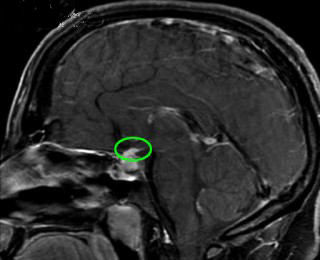

本病的病因尚未完全阐明。由于病理上垂体有明显的淋巴细胞浸润,部分病人血中可检出抗垂体抗体,故目前认为本病可能因自身免疫所致。但是,抗垂体抗体的检出率并不高。晚近,桥本等分析1962~1995年间文献中报道的124例淋巴细胞性腺垂体炎(其中100例经病理证实),发现只有7例抗垂体抗体阳性,抗垂体抗体阳性率较低与所用检测方法(免疫荧光法)不够敏感有关。此外,不少病人同时存在其他内分泌腺的自身免疫性炎症,这也支持本病系自身免疫所致的观点。

关于自身免疫的原因,目前尚不很清楚。由于绝大多数病人为妊娠或产后的妇女,因此有学者认为自身免疫可能与妊娠有关。妊娠时(特别是晚期妊娠)垂体肿大、血供增加,易于发生一些微小的损伤,从而使垂体抗原暴露;此外,妊娠还会引起机体免疫状态的变化,使机体易于产生自身免疫反应。其他一些自身免疫性内分泌疾病(如沉寂性甲状腺炎)也好发于妊娠期,支持妊娠与自身免疫有关的观点。曾有人报道本病可发生于颅内病毒感染后,故本病的自身免疫反应可能与病毒感染也有一定关系。

在本病的发病机制尚不清楚。据文献分析,多数作者认为是一种自身免疫疾病。由于妇女在妊娠期垂体会增生肥大,产后垂体慢慢缩小,释放了大量垂体抗原,促使产生自身免疫反应,淋巴细胞浸润垂体;引起垂体组织破坏。另外,Vanneste曾报道1例49岁妇女,在患病毒性脑膜炎后,发生垂体功能低下,1年后手术证实为淋巴细直接感染垂体引起的。本病有许多病历与其他免疫病同时发生,很有可能与遗传因素有关。